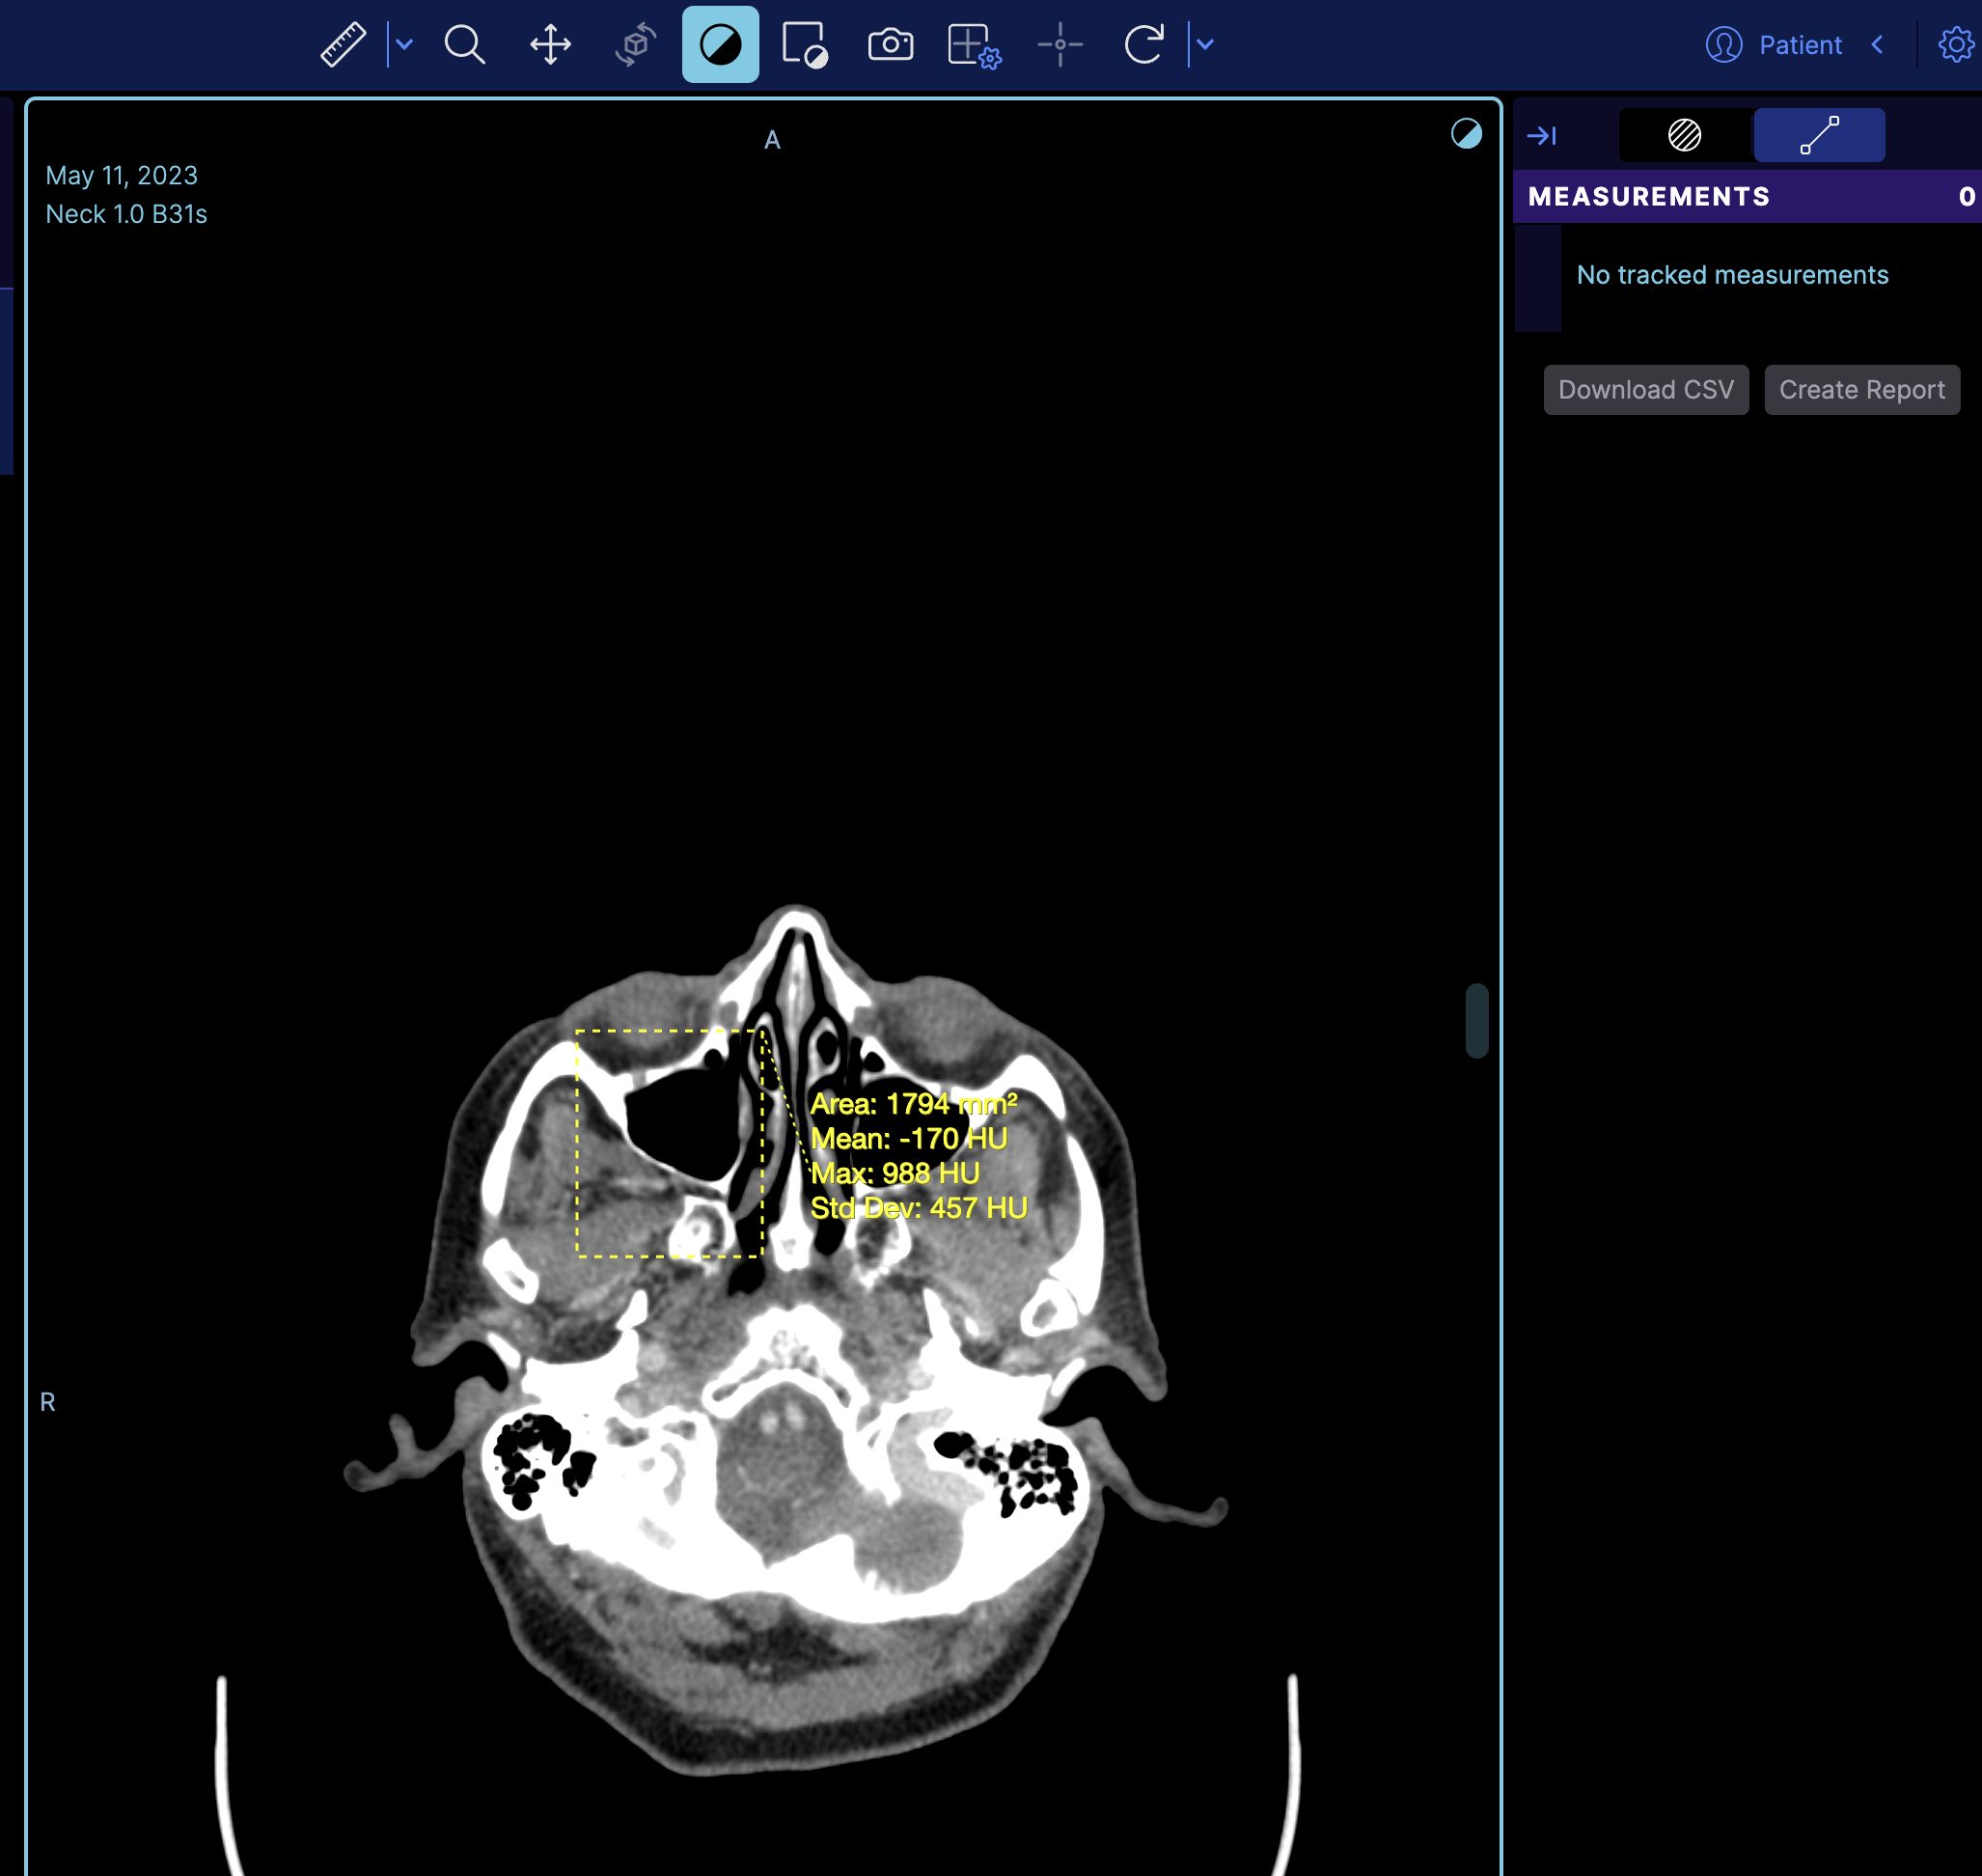

But if you notice it does not appear on the right panel, the reason is that the right panel is the tracking measurement panel. You can switch to a non-tracking measurement by changing

rightPanels: [dicomSeg.panel, tracked.measurements],

to

rightPanels: [dicomSeg.panel, '@ohif/extension-default.panelModule.measure'],

which then it will look like